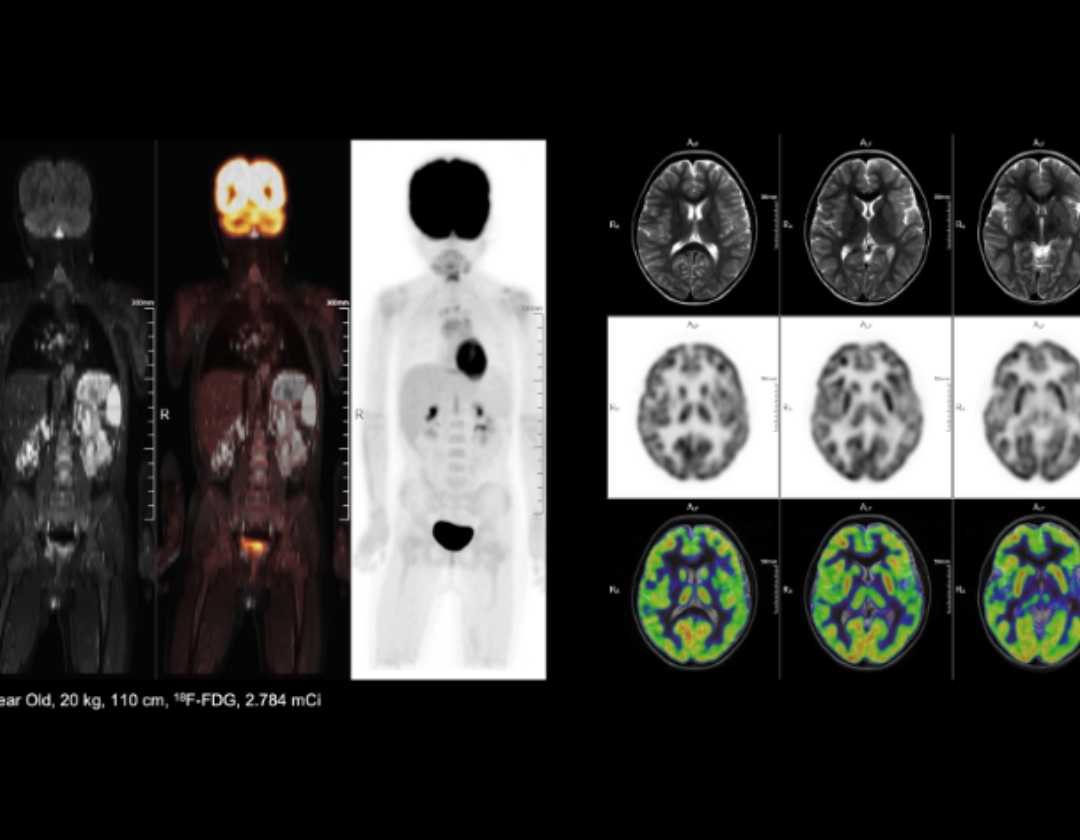

MF-DOPA used for diagnosing Parkinson's disease populations

9 min high resolution whole-body PET/MR exam with low radiation dose